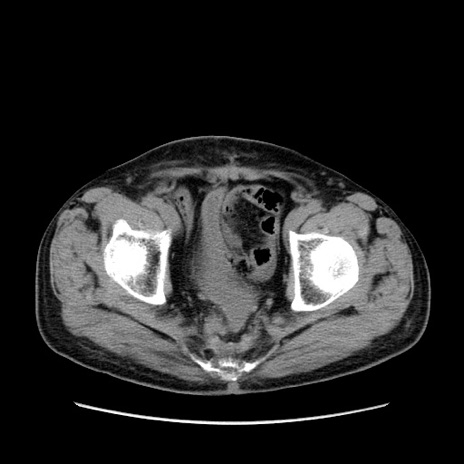

症例24(横断像)

【症例】80歳代男性

【主訴】左側腹部痛、嘔吐

【現病歴】本日早朝より左腹部に痛みあり。昼頃嘔吐認めたため、救急要請。

【既往歴】直腸癌(Mile手術)、胆摘

【身体所見】意識清明、BT 35.9℃、BP 221/93mmHg、SpO2 97%(RA) 、腹部:左ストーマ周囲に限局性の腹部膨隆あり。 膨隆部自発痛・圧痛あり・軟。

【データ】WBC 7700、CRP 0.09